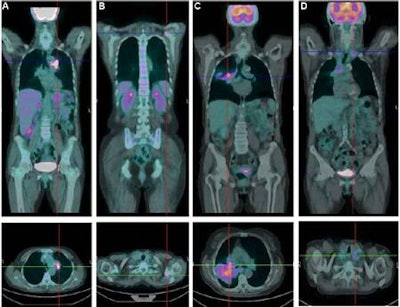

Using FDG-PET/CT, researchers in Italy have found a correlation between cell-free tumor DNA circulating in the bloodstream and the aggressiveness of tumors in patients with advanced non-small cell lung cancer (NSCLC), according to a study published in the November issue of the Journal of Nuclear Medicine.

The study included 24 men and 13 women between the ages of 51 and 80 years who had never been treated with chemotherapy. Morbelli and colleagues found a direct correlation between the amount of cell-free DNA and tumor metabolism -- but not with metabolic tumor volume.

The researchers also reported that a subgroup of 13 patients with metabolically active bone lesions had higher levels of cell-free DNA. While cell-free DNA correlated with tumor metabolism, no association was found with circulating tumor cells.